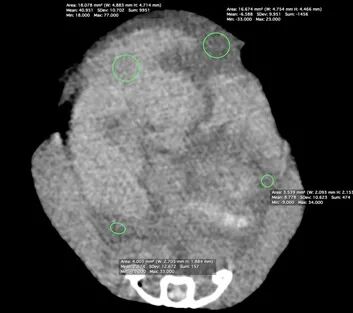

CT平扫:

躯干平扫:双侧肺部存在明显CT值升高区域,右侧较严重。体腔脏器周边存在较多CT值约2HU的均一性物质。肝脏CT值约40HU,肝脏轮廓略钝圆。后腔静脉直径最粗处约10mm。心脏轴面约26*23mm。